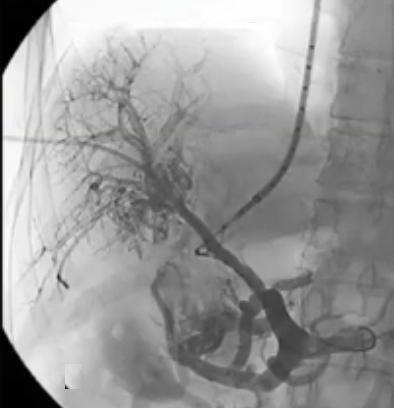

急性病例,已有肠道缺血的迹象,经皮穿刺入路,尿激酶溶栓(t-PA),血流不畅,转为经颈静脉肝内门体分流术(TIPS),抗凝治疗

急性门静脉血栓(续) 对于那些成功实施经颈静脉经肝到达门静脉内急性血栓内,并进行了溶栓和抗凝治疗的患者,是否应该进行经颈静脉肝内门体分流术(TIPS)呢(放支架)? 这一问题存在争议。 。一个过于激进的TIPS手术,导致门静脉分支没有血流,从而发展成肝硬化 妥协的操作是设置一个“小TIPS”,即放置一个直径较细(直径5毫米左右)的TIPS裸支架,溶栓导管经支架通过,进行抗凝和溶栓治疗后,同时保留 TJ 对 SMV/PV 的访问权限,以防再次发生血栓情况。 一例术后急性门静脉血栓病例,最终影像显示门静脉根部血流情况良好,这还不够理想,担心会再次发生血栓,且门静脉压(PSG)超过 12 毫米汞柱,因此增加了经导管动脉溶栓术(TIPS)的治疗方案。